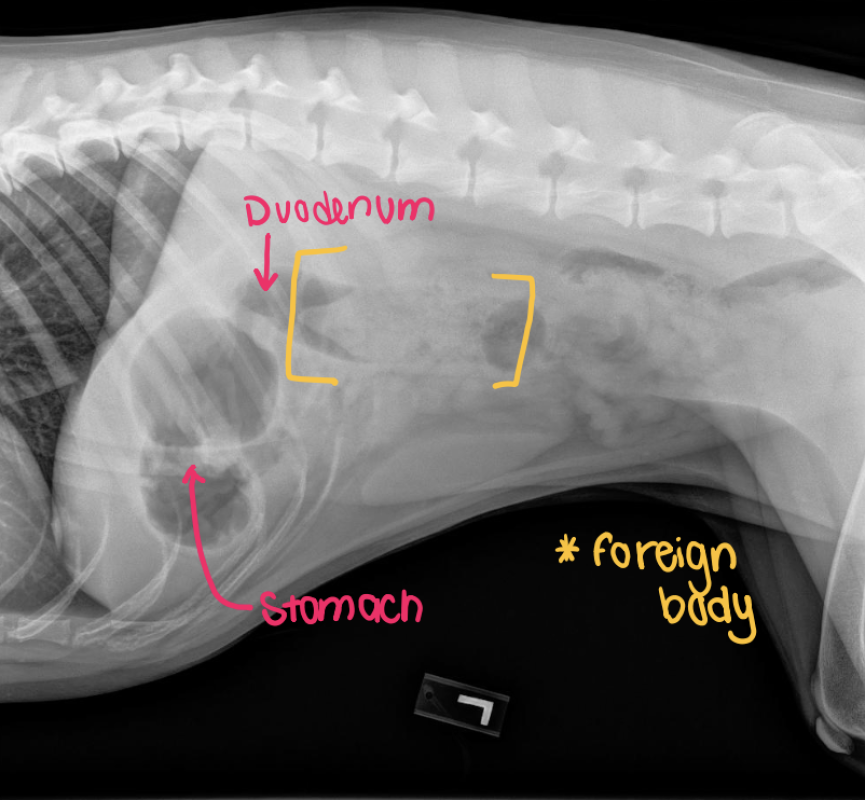

Abdominal radiographs were sent to IDEXX to be read by a board-certified radiologist.

Conclusions: Foreign material was identified in the proximal duodenum. Mild reduction in size of the liver was also noted which could be a normal variation for this animal.

Recommendations: Abdominal exploration was recommended.